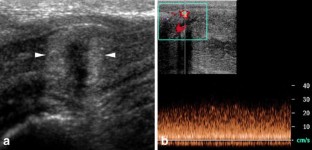

Fig. 4